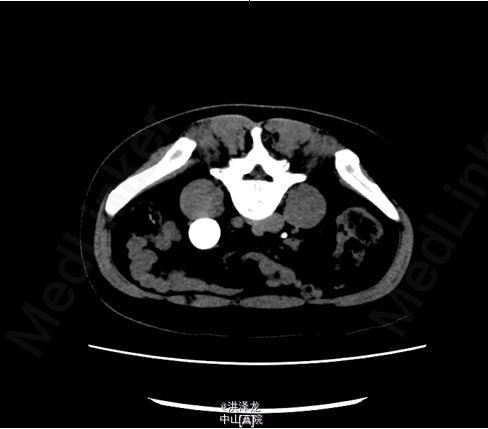

患者,女性,46岁。下腹胀痛半年。患者于6月前无明显诱因出现下腹部闷痛不适,无尿频、尿急、尿痛,无排尿困难,无血尿、脓尿,在当地医院行B超检查提示:左侧巨输尿管伴左肾 积液。现为进一步诊治收入我科。

双肾区无红肿、隆起,左肾区叩击痛(-),右肾区叩击痛(-),左侧肋脊点、肋腰点压痛(-),右侧肋脊点、肋腰点压痛(-)。腹平软,左侧输尿管走行区压痛(-),右侧输尿管走行区压痛(-),膀胱区无膨隆,压痛阴性。 CTU检查提示:左输尿管中段约平S1水平管腔稍变窄,其以下输尿管通畅,并进入膀胱内,其以上输尿管迂曲、扩张,扩张程度大致同前; 肾功能检查:左肾灌注正常,总体功能基本正常,左上尿路机械性梗阻

诊断:左侧巨输尿管。经术前准备后,行腹腔镜下左侧输尿管再植术,手术顺利,术后恢复较好。